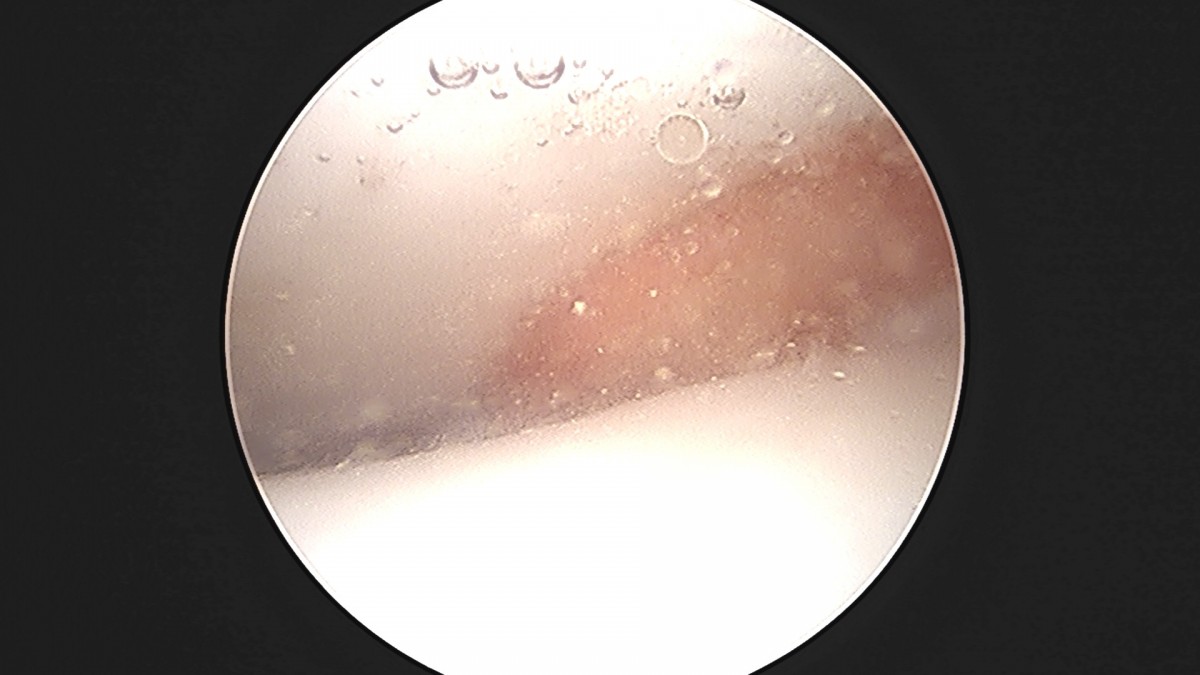

정지영원장님 발목 인대 봉합술 채이O 환자

dae765e4d9ac96aee867c9d6292d8784_1758009749_0224.jpg

dae765e4d9ac96aee867c9d6292d8784_1758009749_6343.jpg

dae765e4d9ac96aee867c9d6292d8784_1758009750_2034.jpg

dae765e4d9ac96aee867c9d6292d8784_1758009750_7737.jpg

dae765e4d9ac96aee867c9d6292d8784_1758009751_3664.jpg

dae765e4d9ac96aee867c9d6292d8784_1758009751_9522.jpg

dae765e4d9ac96aee867c9d6292d8784_1758009752_547.jpg

dae765e4d9ac96aee867c9d6292d8784_1758009753_118.jpg

dae765e4d9ac96aee867c9d6292d8784_1758009753_7115.jpg

dae765e4d9ac96aee867c9d6292d8784_1758009754_3805.jpg